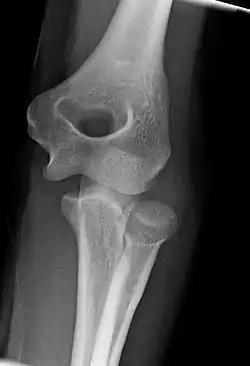

Right: AP X ray of a dislocated right elbow

Fractures

There are three bones at the elbow joint, and any combination of these bones may be involved in a fracture of the elbow. Patients who are able to fully extend their arm at the elbow are unlikely to have a fracture (98% certainty) and an X-ray is not required as long as an olecranon fracture is ruled out.[27] Acute fractures may not be easily visible on X-ray.[28]

Dislocation

Elbow dislocations constitute 10% to 25% of all injuries to the elbow. The elbow is one of the most commonly dislocated joints in the body, with an average annual incidence of acute dislocation of 6 per 100,000 persons.[30] Among injuries to the upper extremity, dislocation of the elbow is second only to a dislocated shoulder. A full dislocation of the elbow will require expert medical attention to re-align, and recovery can take approximately 6 weeks.